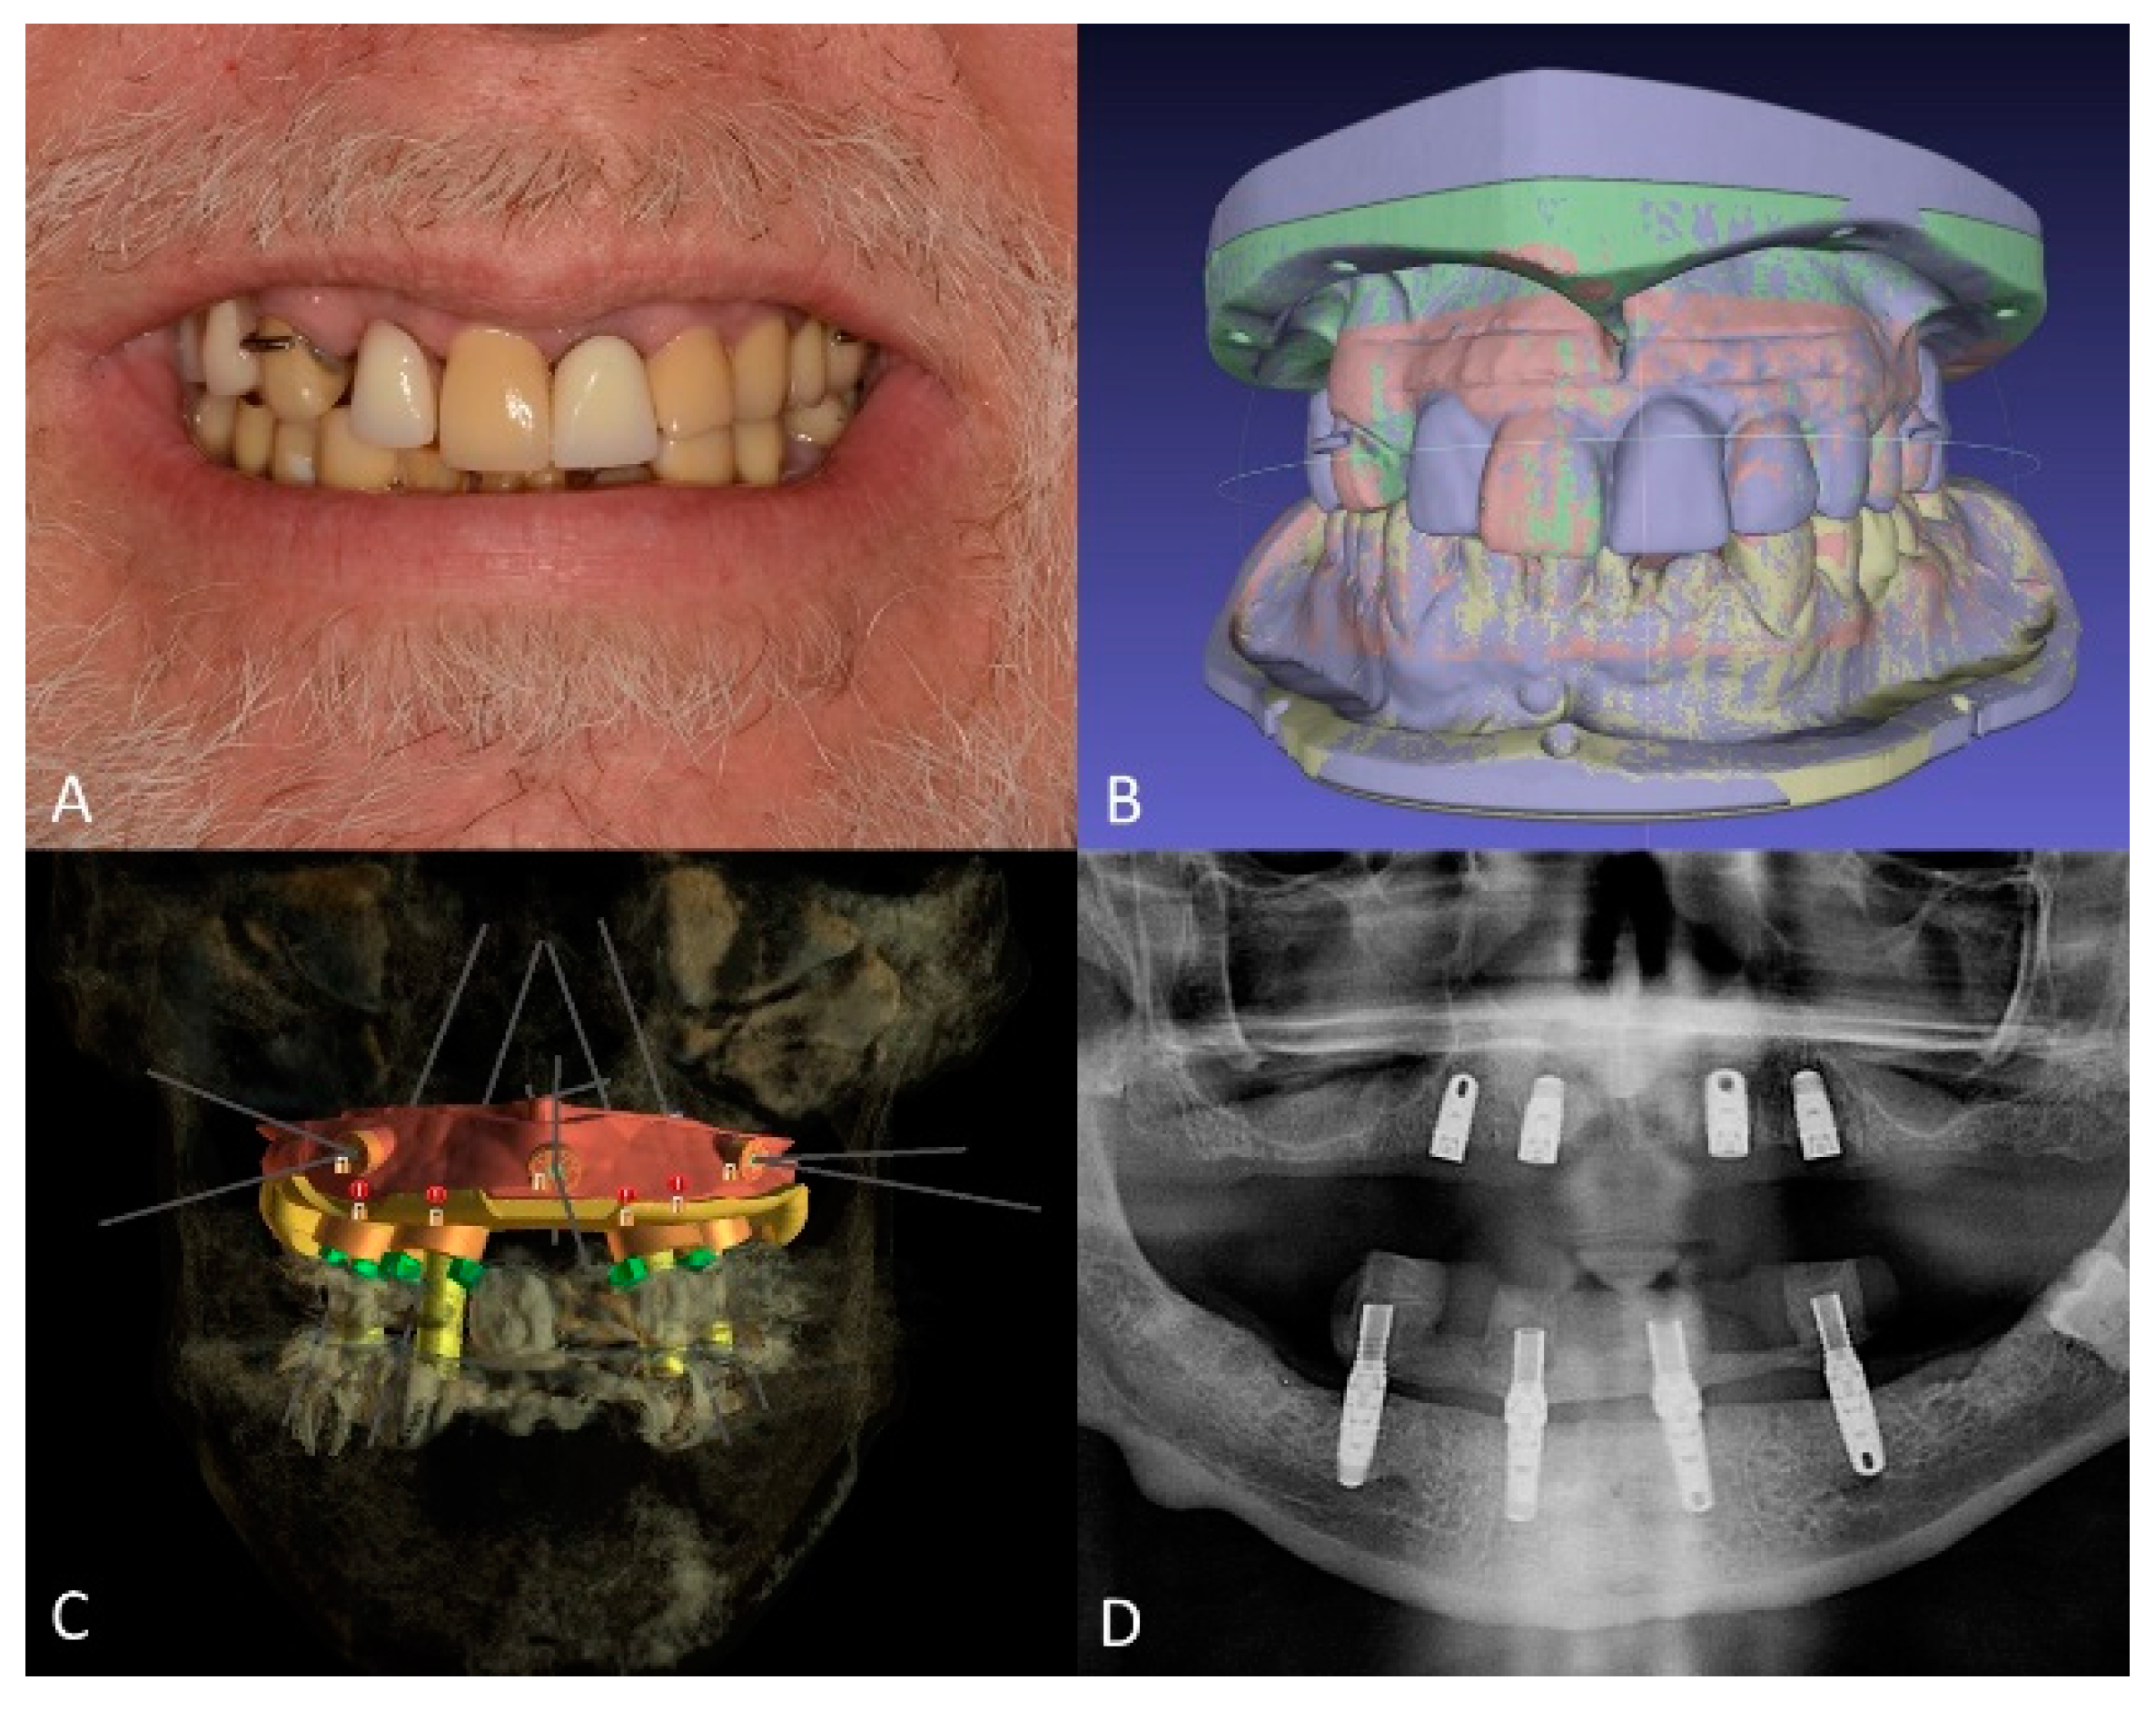

Maxillary and mandibular diagnostic teeth arrangements were fabricated with denture teeth (Blue-Line; Ivoclar Vivadent Schaan, Liechtenstein, Switzerland) and visible-light cure (VLC) denture bases (Triad VLC Denture Base Material; Dentsply Sirona North America, York, PA, USA) to establish the desired incisal edge position and future occlusal plane (Figure 4A). Additionally, the distance from the incisal edges to the lower border of the upper lip during a maximum smile was recorded and inscribed on the diagnostic casts to plan the position of the maxillary implants so that they would be 4 mm above the upper lip during function and smiling to ensure the concealment of the future prosthesis-tissue junction [33,34]. Subsequently, the diagnostic casts and diagnostic artificial teeth arrangements were scanned using a benchtop 3D scanner (E3 Scanner; 3Shape A/S, Copenhagen, Denmark) and were merged with the patient’s CBCT data in an implant planning computer program (BlueSky Plan V4; Blue Sky Bio, Libertyville, IL, USA) (Figure 4B). The placement of four standard-diameter dental implants (Tapered Screw Vent 4.1 × 10; Zimmer Biomet, Parsippany, NJ, USA) for the maxillary arch and four standard-diameter dental implants (Tapered Screw Vent 4.1 × 1 1.5 and 4.1 × 10 mm; Zimmer Biomet, Parsippany, NJ, USA) for the mandibular arch was planned digitally (Figure 4C), and a surgical template was designed in the same computer program. Subsequently, maxillary and mandibular bone reduction guides and bone-supported surgical templates were manufactured using a clear photopolymer (Surgical Guide V2; FormLabs, Somerville, MA, USA) in a stereolithographic (SLA) 3D printer (Form2; FormLabs, Somerville, MA, USA). Additionally, maxillary and mandibular interim complete dentures were fabricated by compression molding using heat polymerized polymethylmethacrylate (PMMA) denture base resin (Lucitone 199; Dentsply Sirona North America, York, PA, USA). On the day of the surgery, the dental implants were placed uneventfully using the computer-generated surgical templates, and the mandibular prosthesis was immediately loaded (Figure 4D).

Figure 4.

Treatment planning. (A), diagnostic artificial teeth arrangement. (B), 3D diagnostic models aligned in 3D modeling software. (C), planned dental implant positions, and surgical guide design. (D), panoramic radiograph of maxillary and mandibular dental implants immediately after placement.